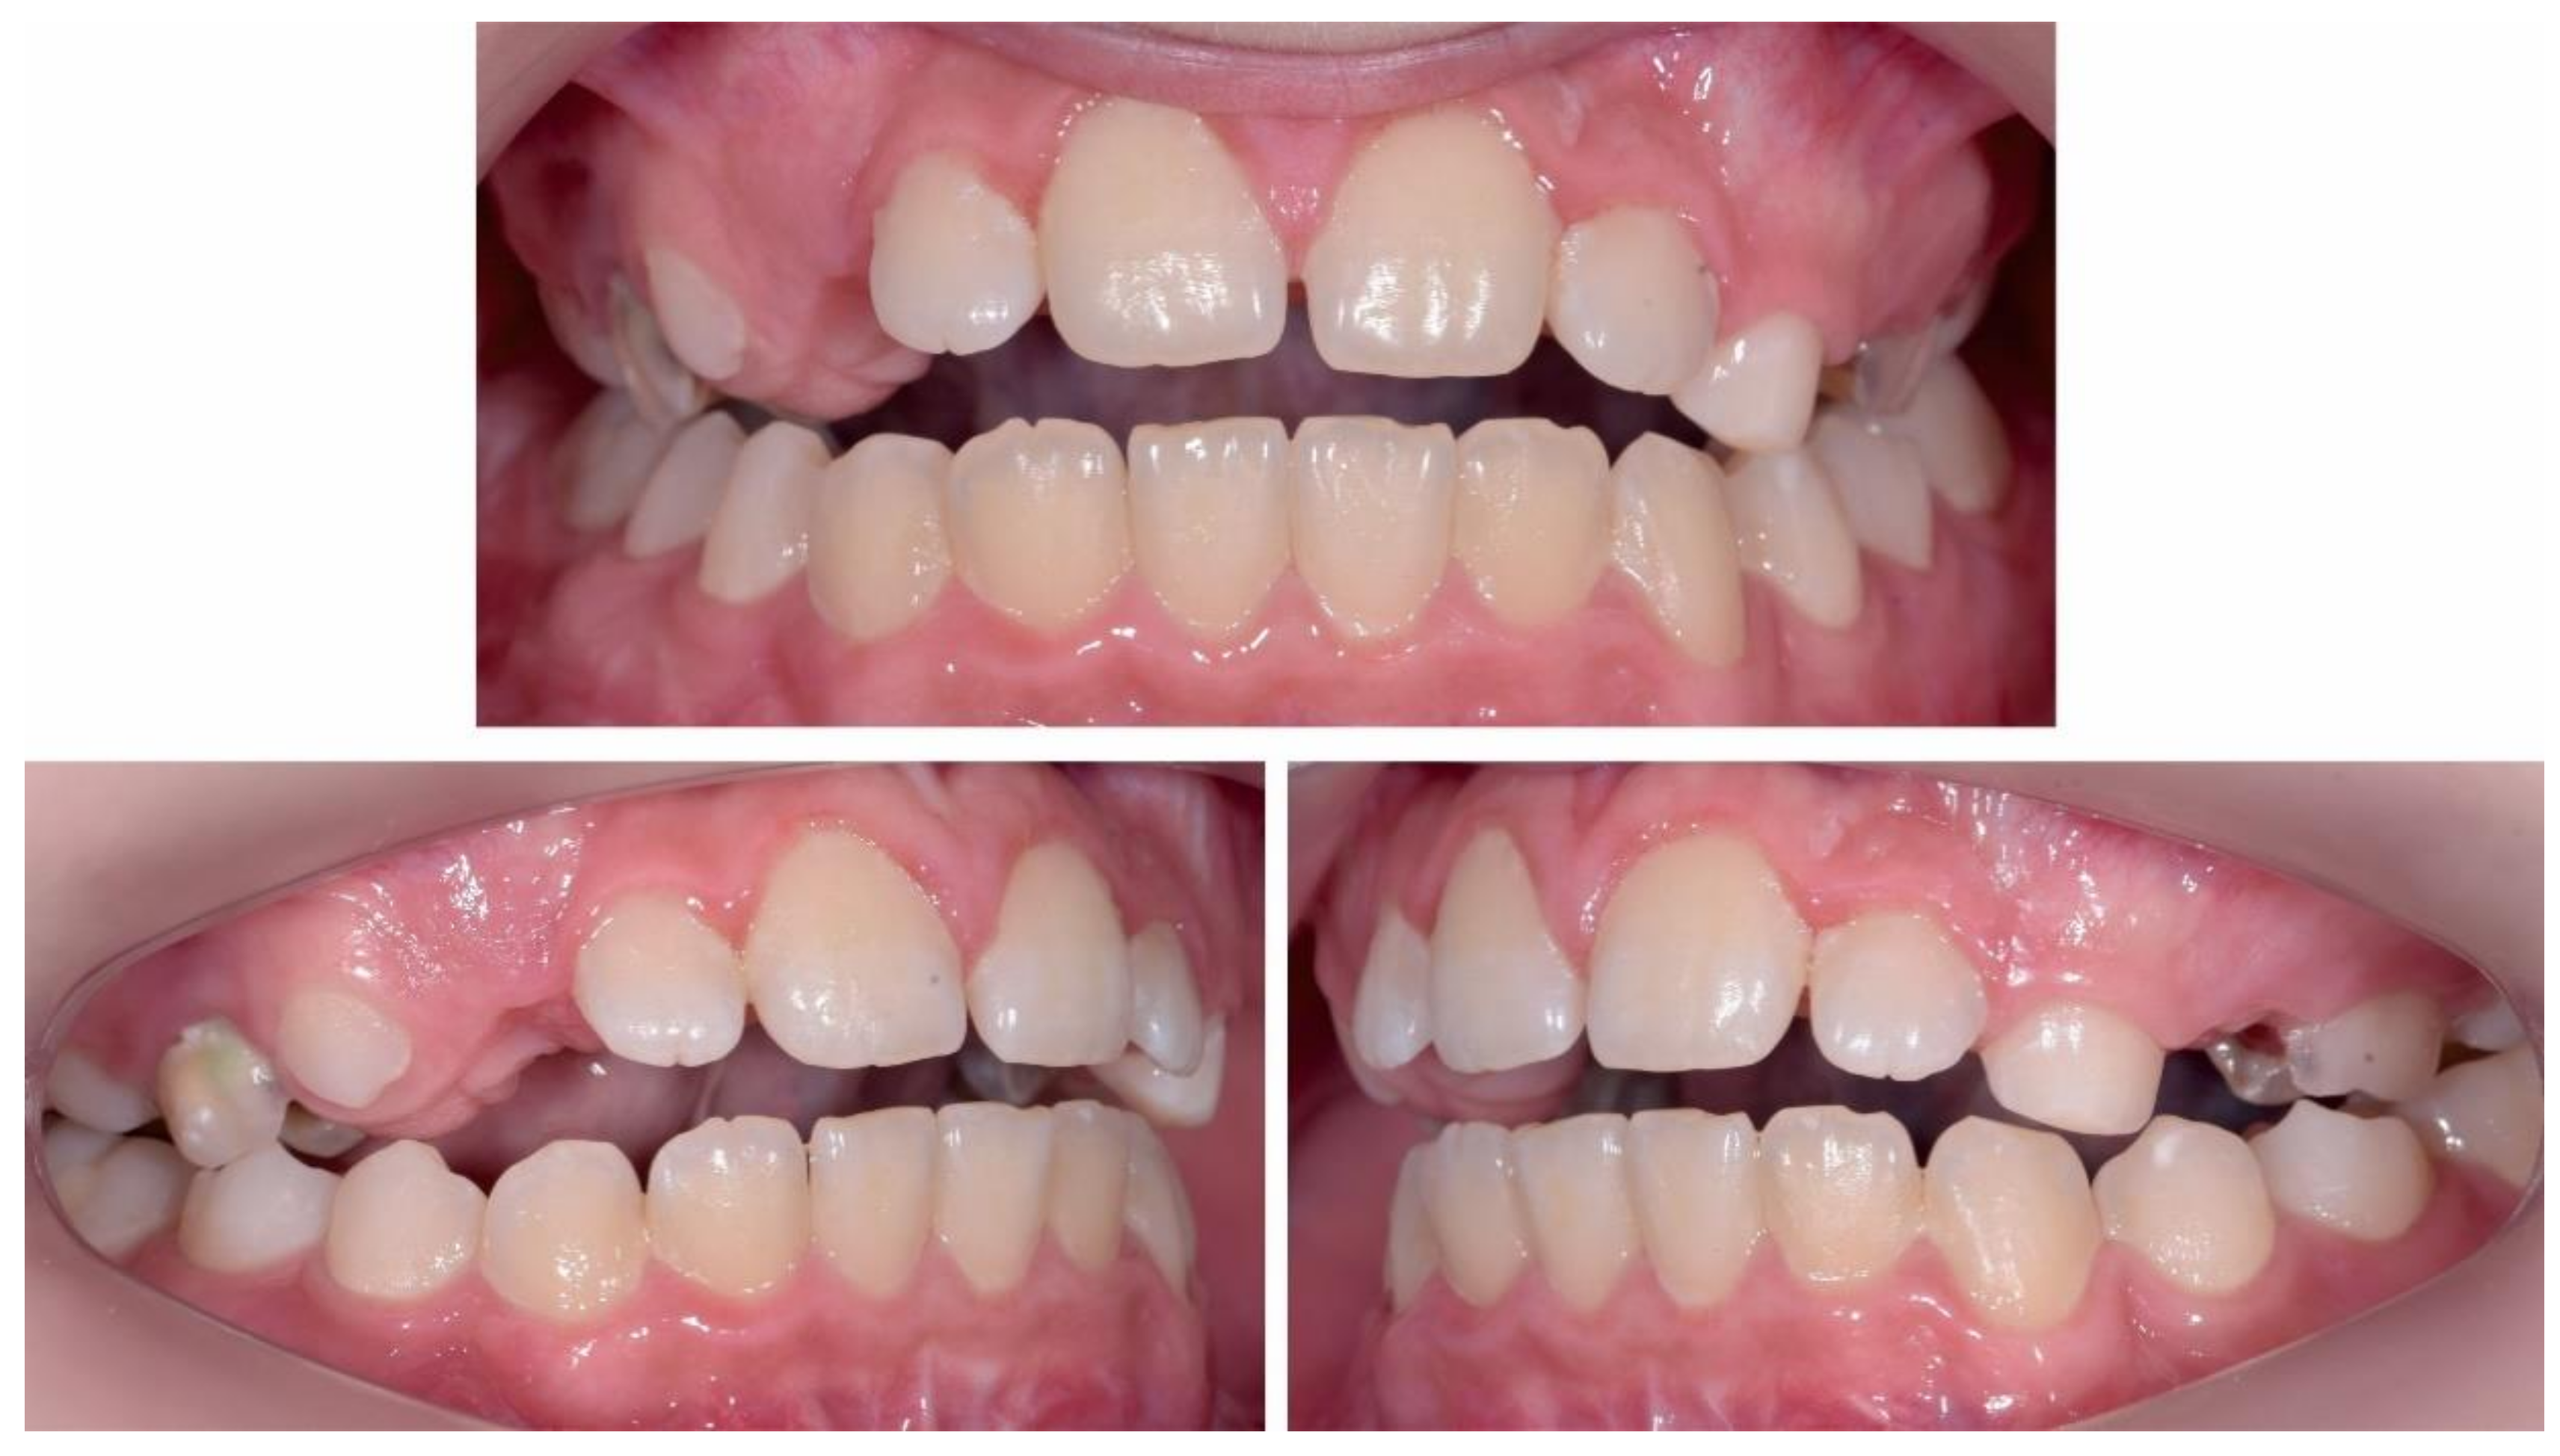

3. Results